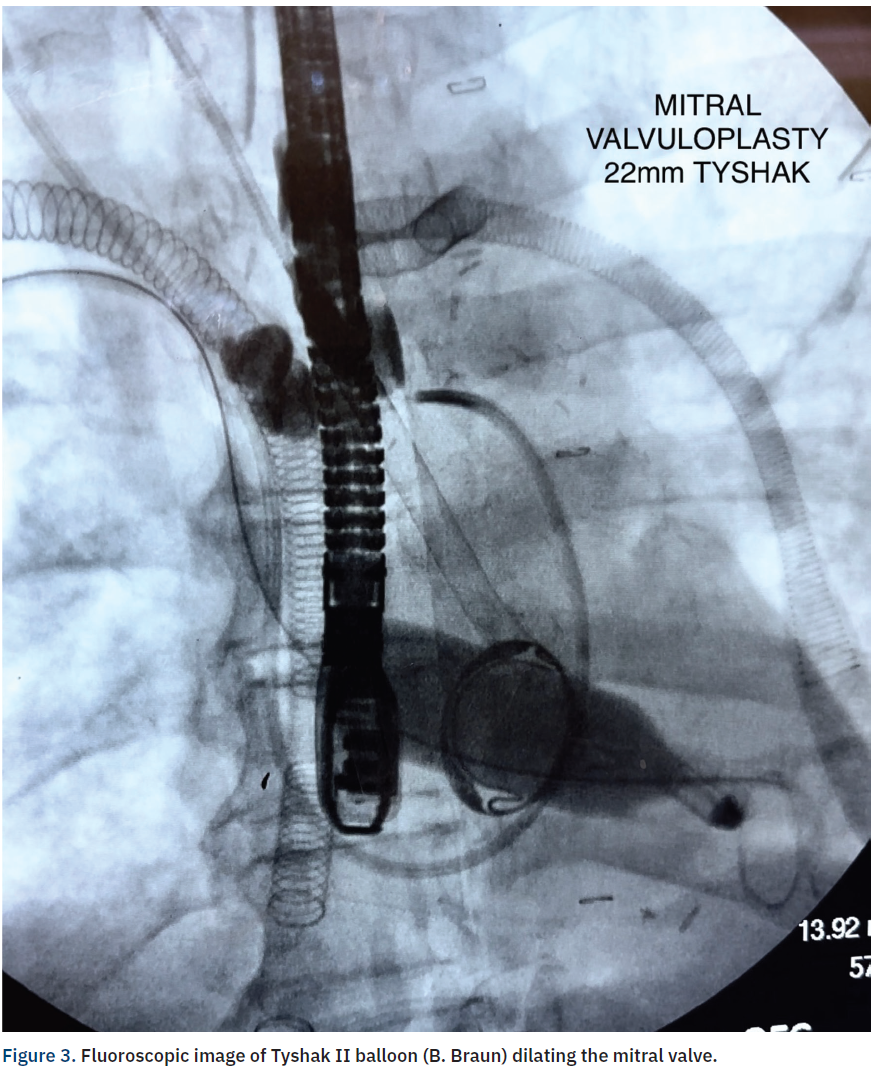

Procedure. After 14 days on VA ECMO and Impella 5.5, echocardiography revealed complete fusion of the bioprosthetic mitral valve leaflets, resulting in severe mitral stenosis (mean gradient of 14 mmHg) and an 0.3 cm2 valve area. The patient was deemed high risk for repeat surgery due to comorbidities and a minimally invasive approach was pursued. Mitral valvuloplasty was deemed the appropriate intervention. Via direct cannulation of the right superior pulmonary vein, an 8 French 23 cm Avanti+ (Cordis) was advanced into the left atrium (Figures 1-2). A Confida wire (Medtronic) was then advanced into the left ventricle. A 22 mm x 5 mm Tyshak II balloon (B. Braun) was placed across the mitral valve (Figure 3) and adequately inflated, resulting in immediate improvement in valve function (mean gradient 3 mmHg) and a valve area of 1.5 cm2. The pulmonary vein was closed with a 4-0 Prolene purse-string suture. Intraoperative echocardiography demonstrated significant leaflet motion improvement (Figure 4). Subsequently, the patient’s hemodynamics improved and ECMO was removed. The Impella was removed nine days later. Two weeks later, the patient developed sepsis that was treated with multiple antibiotics and he unfortunately expired.